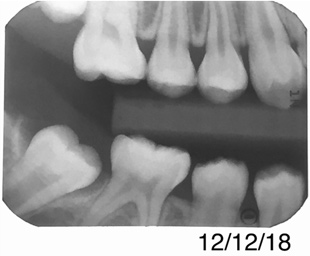

A 28-year-old woman, who previously had braces, had circumferential gumline decalcification (Figure 1) and wished to arrest lesions before they worsened (bitewing, Figure 2). The following protocol is consistent with the product instructions for the resin infiltration material from DMG America, which is the only commercially available resin infiltration system in the US.

Figure 13 shows a bitewing of a 7-year-old girl with Williams syndrome who had previously required treatment under general anesthesia (GA) in a hospital setting for treatment of caries in her primary teeth. An incipient lesion on the mesial of her lower right permanent first molar, tooth No. 30, was treated more conservatively, in office, with resin infiltration, which allowed her to avoid more invasive treatment and the possible need for another GA. The lesion was arrested (Figure 14) and has been stable for over 5 years.

Fig 2.  Circumferential gumline decalcification (Fig 1) and bitewing (Fig 2) of a 28-year-old woman.

Figure 2

Fig 13. Bitewing of a 7-year-old girl. F

Figure 13